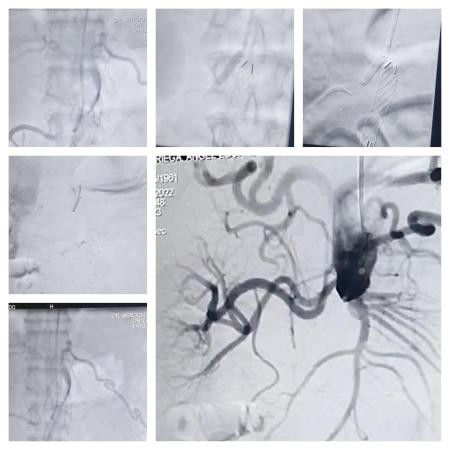

El Dr Sergio Ludueña explicó: “Nosotros ingresamos por el brazo hasta la ingle derecha con catéteres y cuerdas. Los elementos van abriendo el paso para dilatar con balones en forma progresiva, y posteriormente se le coloca la endopróteisis para impermeabilizar la aorta. Con esto generamos un eje de flujo hacia la pierna derecha”.

“Una vez que se abre eso, se realiza un bypass que va a cruzar a la otra pierna para lograr una perfusión que permita mejorar la calidad de vida del paciente, mejorando la circulación en sus extremidades, ya que el paciente se encuentra en silla de ruedas”, afirmó el hemodinamista del INCOR.